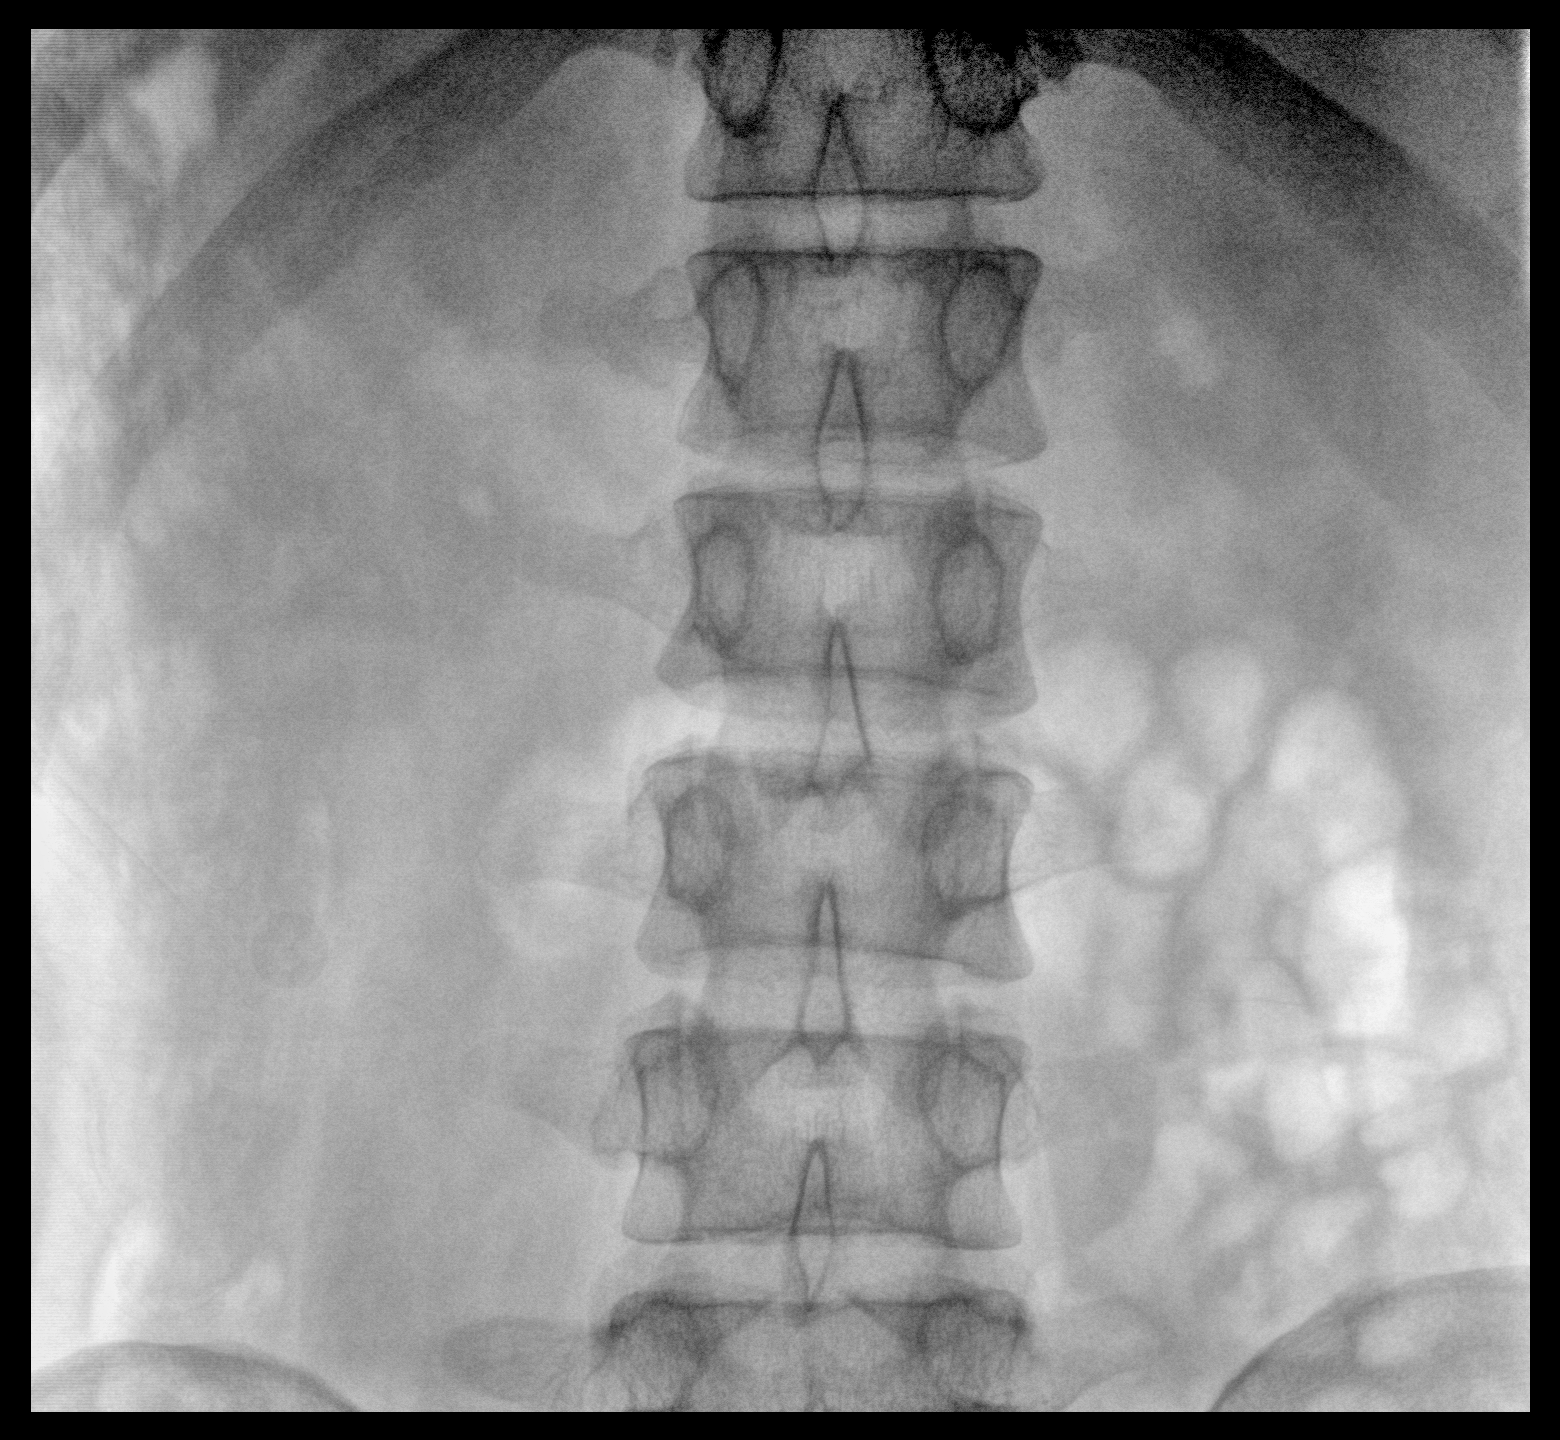

臨床適用科室:骨科、普通外科、矯形外科、創(chuàng)傷外科、泌尿外科、脊柱外科、疼痛外科、消化科、婦科等科室。

大尺寸動態(tài)平板探測器,高DQE、低噪聲、圖像清晰。采用多分辨率圖像增強(qiáng)處理技術(shù),不同部位不同圖像處理算法,滿足客戶多樣化的需求。

采用智能變頻脈沖透視技術(shù),優(yōu)化圖像質(zhì)量的同時降低輻射劑量,呵護(hù)醫(yī)患健康